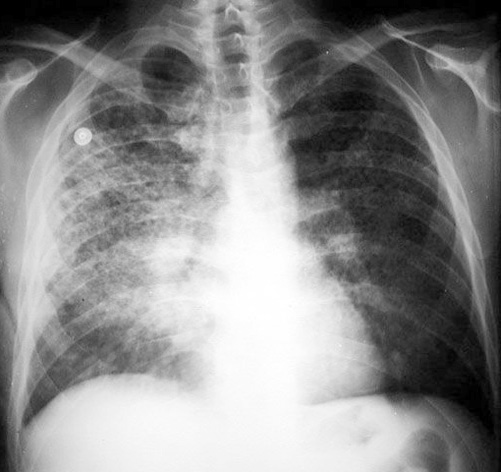

Honeycombing

• Seen in end stage lung disease

• Indicative of diffuse interstitial fibrosis

• Due to bronchiolectasia

• Most of the time in bases

• Upper lobe distribution seen in eosinophilic granuloma